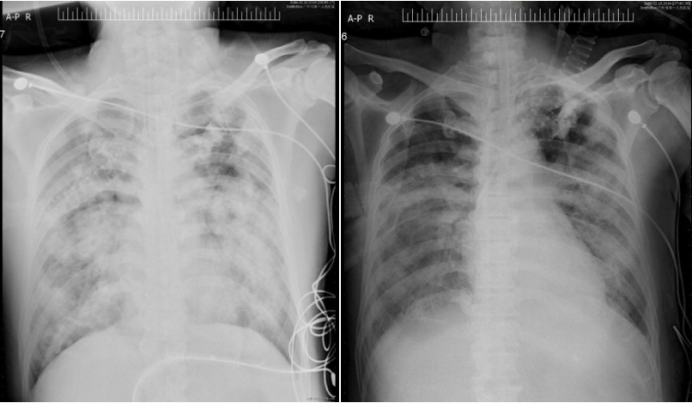

病例7:49岁女性患者,因反复咳嗽咳痰1年、咳血丝痰伴气促20余天入院,入院后需端坐呼吸,气促明显,高流量氧疗情况下SpO2仍低于80%。胸部CT提示右肺上叶尖段周围型肺癌伴全身多发转移;支气管镜检查示气管下段肿瘤外压性狭窄并侵犯黏膜,双侧支气管开口狭窄,进镜后患者呼吸困难加重,紧急气管插管机械通气,随后在左主支气管入金属支架(图11),快速解除气道阻塞。左主支气管支架入术后反复大量脓血痰病理诊断为低分化腺癌,ALK基因变异。患者反复发热、低氧发作,需反复纤支镜吸痰;双上肢、颜面部浮肿明显,需反复心包、双侧胸腔抽液;白细胞明显升高、贫血,间断需升压药维持血压;停机不耐受(3~5 min)。患者经过积极的抗感染及基因靶向治疗后,病情逐渐好转,成功拔管并脱离呼吸机支持,顺利转出RICU。复查纤支镜提示气道通畅、炎症明显改善(图12),影像学改善(图13)体力状况PS评分显著下降,达到临床稳定水平,随后接受后续抗肿瘤综合治疗

图片

11  患者胸部CT及纤支镜下置入支架

12  出院前复查纤支镜

13  治疗前后胸部CT对比